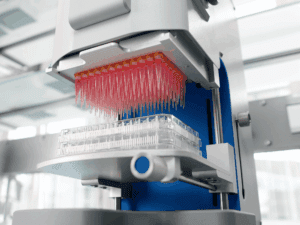

Our 96- and 384-well automated platforms enable large-scale screening of thousands of compounds across diverse patient-derived organoids. With real-time monitoring and data collection, we rapidly identify promising leads, accelerating discovery with both scale and precision.